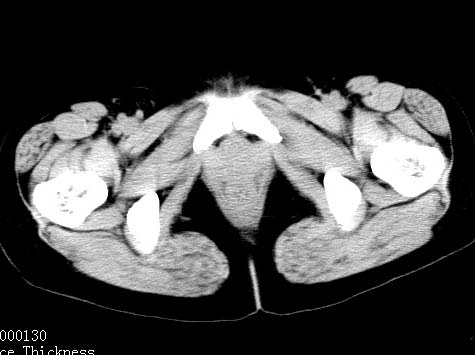

女性 病人 44岁 盆腔 下腹部痛1天!

盆腔内低密度为主混杂等密度及少许囊样与班状钙化影,如果做了肠道准备就好了。支持畸胎瘤。当然做mri会更好

典型的双侧附件畸胎瘤.

盆腔多发畸胎瘤,较为典型。